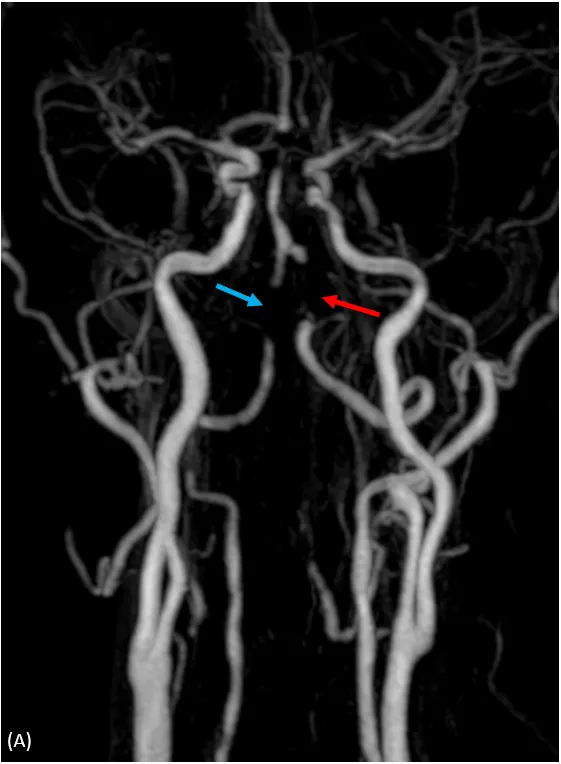

核磁共振血管攝影,顱內左(紅色箭頭)及右(藍色箭頭)椎動脈高度狹窄或是完全阻塞。大里仁愛醫院提供